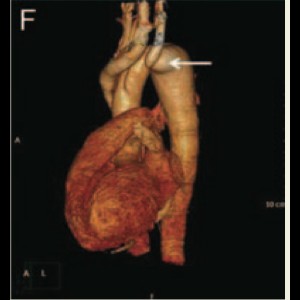

Supra-valvular aortic stenosis in a patient with homozygous familial hypercholesterolaemia

Supra-valvular aortic stenosis in a patient with homozygous familial hypercholesterolaemia

Supra-valvular aortic stenosis in a patient with homozygous familial hypercholesterolaemia

Supra-valvular aortic stenosis in a patient with homozygous familial hypercholesterolaemia